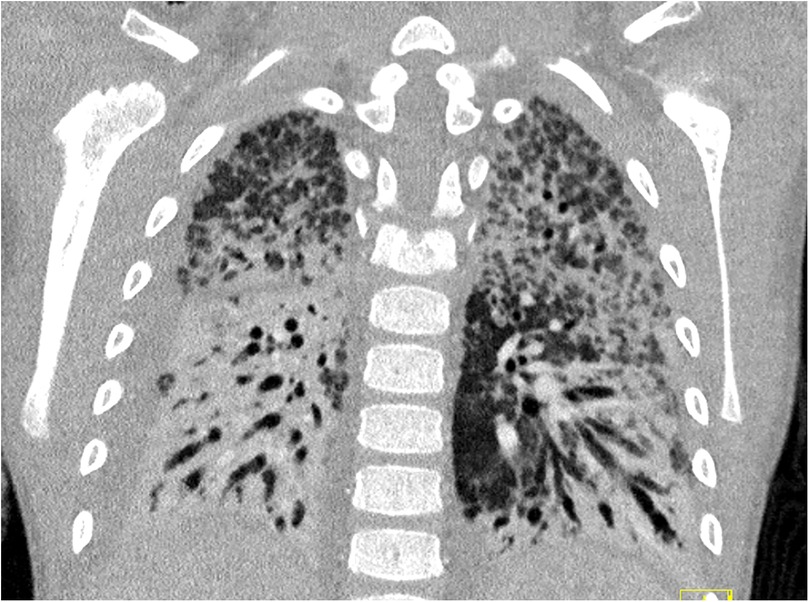

Veno-venous extracorporeal membrane oxygenation (VV-ECMO) is an established rescue therapy for severe pediatric ARDS, but prolonged support is rarely reported. We describe a previously healthy 6-year-old boy who developed Stevens-Johnson syndrome, complicated by progressive respiratory failure and severe ARDS. Despite maximal ventilation, oxygenation remained insufficient, and VV-ECMO was initiated on day 11 of illness. Cannulation was performed via jugular and femoral access, followed by lung-protective ventilation, repeated surfactant administration, corticosteroid therapy according to the Meduri protocol, and ACE inhibitor therapy. ECMO support was complicated by pulmonary fibrosis, cholestatic liver dysfunction with secondary hemochromatosis, and prolonged sedation-associated delirium with subsequent critical illness polyneuropathy. A first attempt to discontinue ECMO after 90 days failed due to presumed pulmonary embolism, requiring recannulation. Ultimately, successful weaning was achieved after 113 days of VV-ECMO. The patient was transferred to a specialized pulmonary and neurological rehabilitation center and discharged home after six months, still dependent on a tracheostomy cannula. At 18-month follow-up, he requires only nocturnal mechanical ventilation through the tracheostomy, attends school, and leads an otherwise normal life. A trial removal of the cannula and closure of the stoma is scheduled for spring 2026. This case illustrates that prolonged VV-ECMO can allow lung recovery in pediatric patients with ARDS secondary to SJS, despite complications. Careful multidisciplinary management and preserved neurological function were key factors supporting long-term survival.